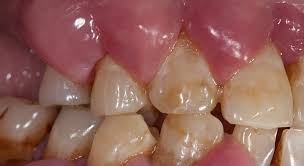

warning signs of periodontitis

accumulation of plaque biofilm and calculus

redness (erythema) and swelling (edema)

gingival bleeding

suppuration (pus)

periodontal pockets

clinical attachment loss and tooth mobility